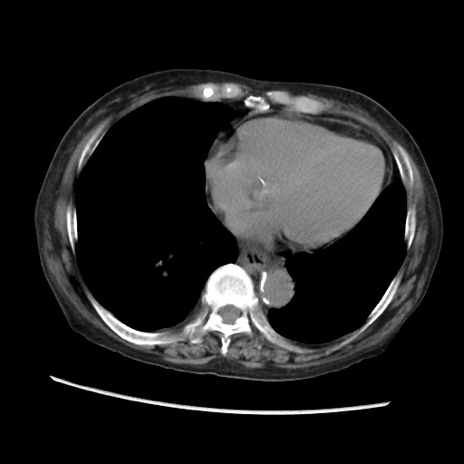

症例31(横断像)

【症例】80歳代 女性

【主訴】腹部膨満感

【現病歴】他院にて肝硬変にてフォロー中。1週間前から便秘、腹部膨満感、臍部腫瘤あり受診となる。

【既往歴】肝硬変

【身体所見】腹部膨隆あり、皮膚変化なし、疼痛なし。

【データ】WBC 4600、CRP 0.25